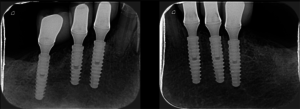

Figura 4 – Controle de um ano através de radiografia panorâmica da reabilitação inferior com implantes Cone-Morse Due Cone (Implaci De Bortoli, São Paulo/Brasil) e coroas unitárias, mantendo os remanescentes dentais do 33 ao 43 também como elementos unitários individualizados.

Figura 5 – Radiografias periapicais de controle de um ano após a instalação dos implantes. Observar a excelente adaptação intraóssea dos implantes cone-morse.